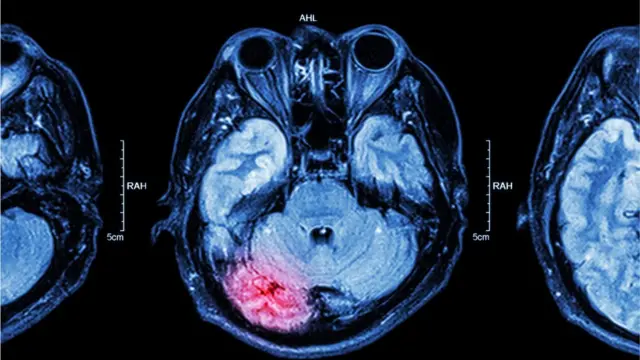

El experimento midió en paralelo la actividad cerebral de los participantes y registró que la reacción de un área conocida como amígdala, en el lóbulo temporal, fue intensa durante el primer engaño.

Con la sucesión de deshonestidades, la actividad en la zona encargada de producirnos un estímulo de incomodidad se debilitaba de manera gradual.

Y mientras mayores las transgresiones, menores las resistencias emocionales.

Pero eso no es todo, a través de la resonancia magnética los científicos lograron predecir los niveles de deshonestidad de los participantes de acuerdo a su actividad cerebral.